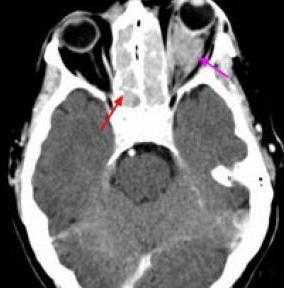

CT,MRI可见到组织肿胀质破坏,有助于了解病变范围,帮助分期。